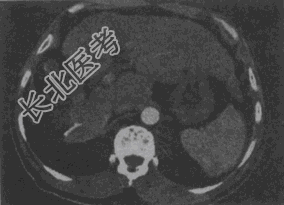

- 单项选择题女,56岁, 腹胀、双下肢水肿、乏力、食欲缺乏,影像所见如下图, 最可能的诊断是

A、酒精性肝硬化并肝血管瘤

B、血吸虫肝硬化并肝癌

C、肝炎后肝硬化并肝癌

D、局限性脂肪肝

E、原发性肝癌